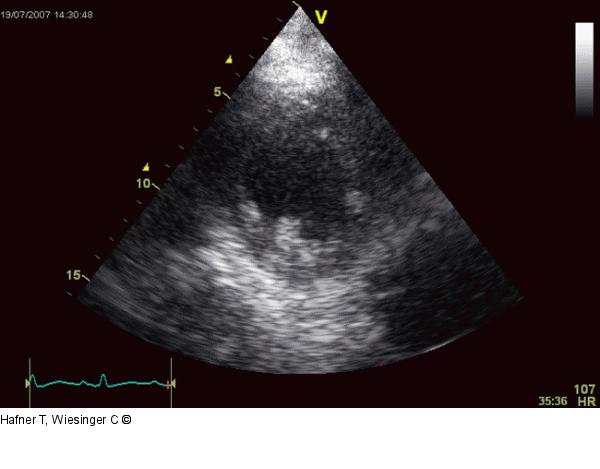

Abbildung 2b: Echo Parasternaler Kurzachsenschnitt postoperativ, oben Enddiastole, unten Endsystole |

Parasternaler Kurzachsenschnitt postoperativ, oben Enddiastole, unten Endsystole |